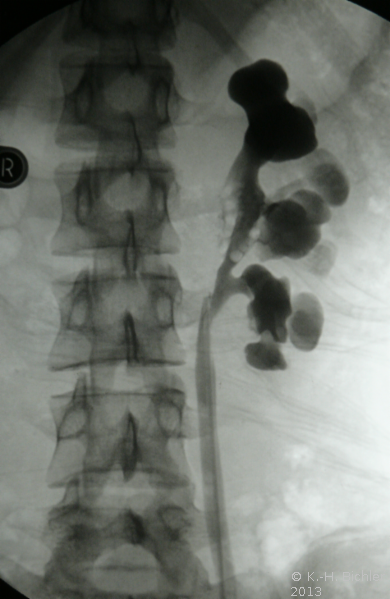

Sonographiebeispiele: Harnstau infolge Ureterabgangsstenosen (Abbildung 6a,b).

Bei Harnstaus ist eventuell eine retrograde Sondierung mit Sicherung einer Ureterabgangsstenose angezeigt (Abbildung 8) (

s. Bildgebende Verfahren/Retrogrades Pyeologramm).